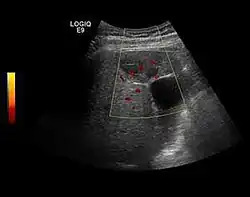

The ultrasound appearance is a well defined lesion, with very thin, almost unapparent walls, without circulatory signal at Doppler or CEUS investigation. The content is transonic suggesting fluid composition. The presence of membranes, abundant sediment or cysts inside is suggestive for parasitic, hydatid nature. Posterior from the lesion the acoustic enhancement phenomenon is seen, which strengthens the suspicion of fluid mass. They typically displace normal liver vessels but no vascular or biliary invasion occurs.

-

Liver cyst -

Hydatid liver cyst. Diagnostic criteria are the presence of membranes and sediment inside.